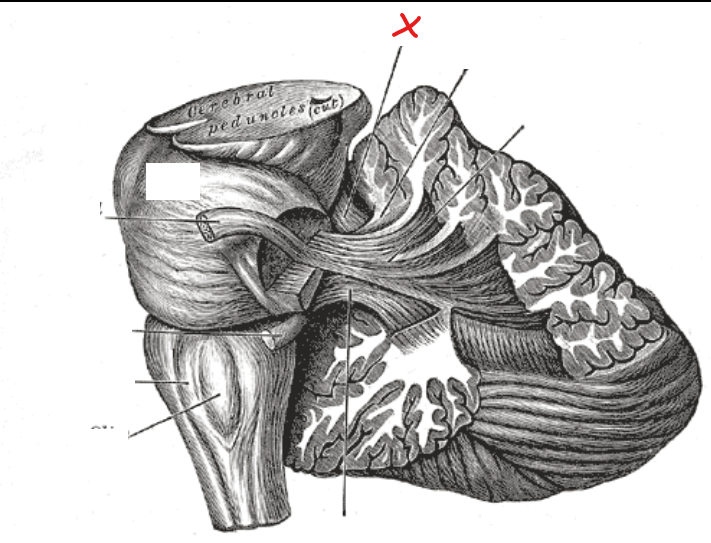

Which part of the midbrain does the trochlear nerve exit from

Dorsal aspect of midbrain inferior to inferior colliculi

What is the site where the midbrain and pons are connected called

Pontomesencephalic junction

What is X

Dorsal median sulcus